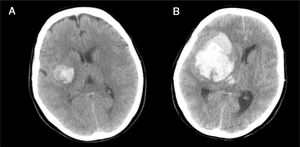

Caso 3Varón de 79 años con pérdida brusca de consciencia en su domicilio. Los servicios de emergencia objetivan un GCS de 4 (O1, V1, M2), pupilas arreactivas y presión arterial de 205/115mmHg. Se procede a realizar intubación traqueal y traslado al hospital; en Urgencias obtiene un GSC de 4 y ausencia de reflejos fotomotor, corneal y oculocefálico. La TC craneal mostró un hematoma intraparenquimatoso en los ganglios de la base derechos, desplazamiento de la línea media e invasión del sistema ventricular (fig. 6). Valorado por Neurocirugía y Neurología, se descartó cualquier tipo de tratamiento. El CT planteó a la familia la posibilidad de la donación de órganos, aceptando esta el ingreso en la UCI para facilitar la donación en ME. A las 48h el paciente se mantenía en coma arreactivo, sin reflejos fotomotor, corneal ni oculocefálicos, pero con persistencia del reflejo tusígeno y de respiración espontánea. La familia no deseaba prolongar más la situación, por lo que se decidió la retirada del soporte ventilatorio. Se les planteó entonces la opción de la donación en asistolia controlada, que autorizaron. Se realizó extracción de riñones y córneas. Los riñones fueron trasplantados, presentando función renal inmediata y buena evolución posterior.